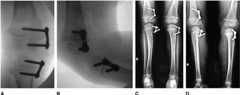

Figure 1.

A–D, Guided growth for a 4-year-old girl with unilateral genu valgum.A andB, Preoperative clinical and radiologic findings. Note the mechanical axis is traversing zone 3.C andD, Radioclinical outcome at 3.6-year postimplant insertion. Note the mechanical axis is optimally corrected, i.e., traversing the lateral half of the central one-third of the widest diameter of the proximal tibia.